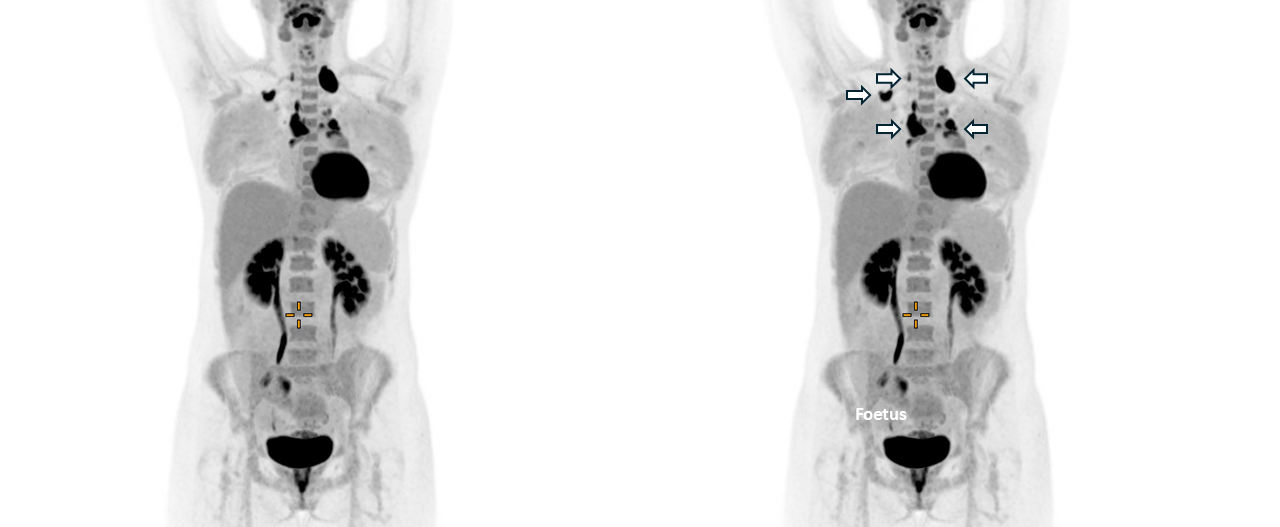

Early clinical research outcomes of the Total Body PET Posted on June 18, 2025June 19, 2025 by Sarah Cole

Sharing the Australian National Total Body PET Facility: a win–win for researchers and clinicians Posted on June 3, 2025June 3, 2025 by Sarah Cole

Transforming medical imaging: Simon Cherry and Ramsey Badawi on total-body PET Posted on October 9, 2024October 9, 2024 by aburton